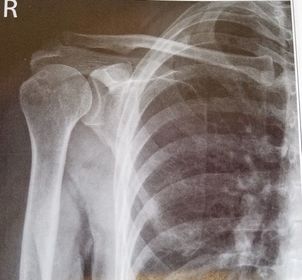

| AP Shoulder | patient is rotated towards the unaffected shoulder: decreased thoracic superimposition over the scapular body |

| AP Shoulder | patient is rotated towards affected side:increased thoracic superimposition over the scapular body |

| AP Shoulder Neutral | ANATOMY: proximal humerus, lateral 2/3 of clavicle, open shoulder joint CRITERIA: humeral epicondyles are 45 degrees to the IR neither tubercle should be seen on the humeral head POSITIONING: CR perpendicular @ 1'' inferior to coracoid process |

| AP Shoulder Internal Rotation | CRITERIA: lesser tubercle in profile medially POSITIONING: CR perpendicular @ 1'' inferior to coracoid process |

| AP Shoulder External Rotation | CRITERIA: greater tubercle in profile laterally POSITIONING: CR perpendicular @ 1'' inferior to coracoid process |